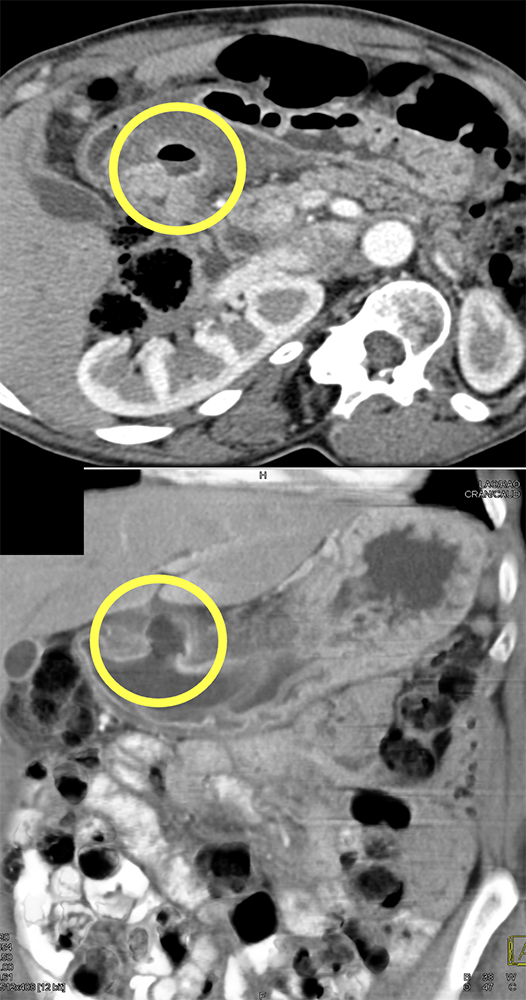

“In our patient, the findings of prominent mucosal folds extending from the pylonic channel on upper gastrointestinal series and the thickened antral wall on CT scans correlate well with the known pathologic appearance of gastnic antral vascular ectasia. Histologically, antral thickening results from a combination of foveolar and fibromuscular hyperplasia. Grossly, the antral fold prominence appears to result from bunching of the mucosa in the thickened, hypercontractile antrum.” Gastric antral vascular ectasia ("watermelon stomach"): radiologic findings. Urban BA, Jones B, Fishman EK, Kern SE, Ravich WJ. Radiology. 1991 Feb;178(2):517-8. |

“Gastric antral vascular ectasia primanily affects women (9:1 female-to-male ratio) aged 56-76 years, and is associated with liver cirrhosis (37%) and achlorhydnia (35%). The usual symptoms are iron-deficiency anemia and melena due to chronic gastrointestinal bleeding from the dilated, superficial, and easily traumatized vessels. Antrectomy is curative, but endoscopic treatment with heat probes or lasers has shown promise.” Gastric antral vascular ectasia ("watermelon stomach"): radiologic findings. Urban BA, Jones B, Fishman EK, Kern SE, Ravich WJ. Radiology. 1991 Feb;178(2):517-8. |